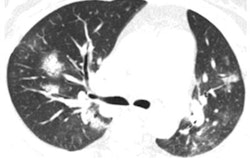

What's more, multiple case reports showed that DNA testing occasionally failed to confirm COVID-19 in individuals whose CT scans indicated the presence of the coronavirus. In response, the Chinese National Health Commission on February 5 announced that it had revised its official diagnosis and treatment scheme for COVID-19 to add "clinical diagnosis" through a set of clinical symptoms and chest CT findings as an auxiliary testing method exclusively for cases in Hubei.

"The nucleic acid test result is the gold standard for the final diagnosis of novel coronavirus infections, but those who have a negative nucleic acid test result may see positive CT imaging results," Dr. Zhang Xiaochun from Zhongnan Hospital of Wuhan University said in a statement released by the National Health Commission. "The [CT-based] method may help ease the difficulty in conducting nucleic acid tests in a short period of time, helping control the epidemic."